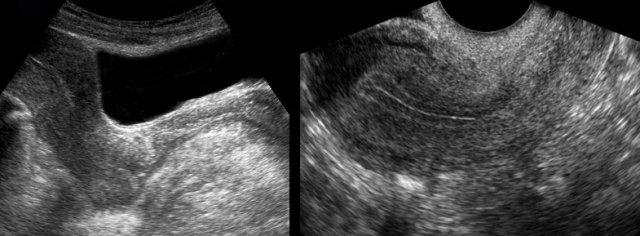

Ở bệnh nhân này được chuyển đến với nghi ngờ thủng dạ dày, một khối máu đông lớn không đồng nhất (đầu mũi tên) trong khoang phúc mạc trái đã được phát hiện (hình trên bên phải).

Một cục máu đông lớn như vậy có thể dễ dàng bị nhầm lẫn với mỡ mạc treo bình thường hoặc quai ruột.

Sự nhận thức và kiểm tra cẩn thận khối này, vốn không có nhu động, là những dấu hiệu hữu ích để phân biệt.

Bệnh nhân này cũng có nhiều dịch tự do, khi chọc hút xác nhận là máu đã hóa lỏng (hình dưới bên phải).

Nội soi ổ bụng phát hiện 1,5 lít máu và thai vòi tử cung bị vỡ.